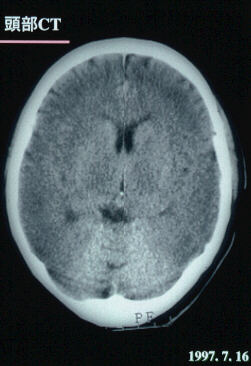

1997.7.16:頭部CTスキャン

脳浮腫持続。